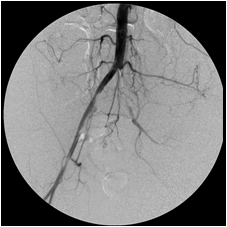

This 41-year-old woman smoked for a long time and developed severe bilateral calf cramping after short walks. Investigation revealed that she had completely occluded her distal abdominal aorta and her right and left iliac arteries, severely restricting the flow of blood into her lower limbs. She was unwilling to have surgery and came to me for minimally invasive treatment. By dripping urokinase (a clot dissolver) over 72 hours through two catheters that I advanced across the occlusions and later stenting the opened arteries, I wholly restored blood flow through her iliac channels. She walked again – without cramps.